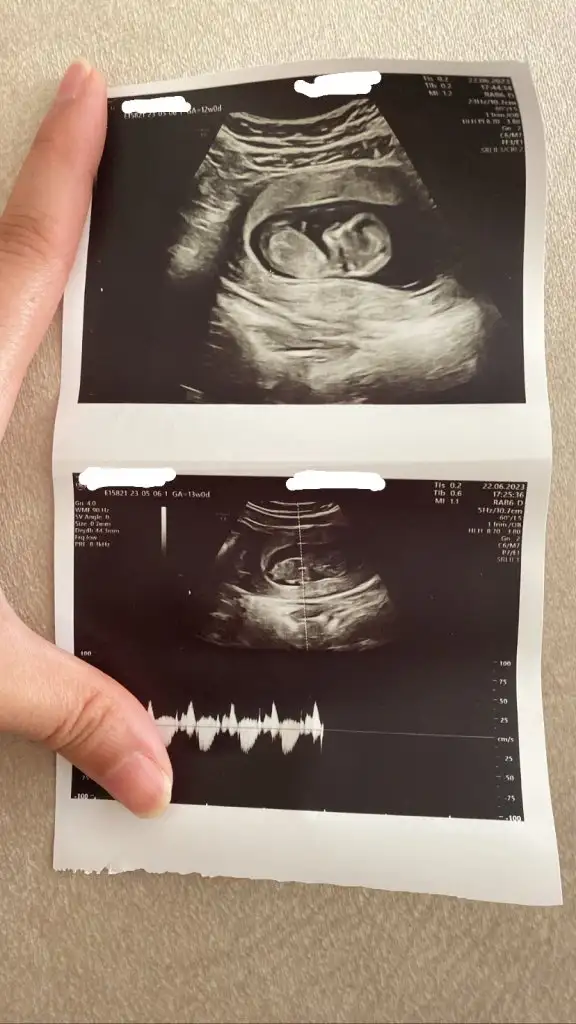

Kızlar dün tam 12 haftalık kontrolüm vardı doktor cinsiyeti görürsem söylememi ister misin tahmini olarak dedi , kız gibi duruyor kendini saklıyor dedi ama 16.haftada diğer kontrolüm net bir şey söylemiyorum dedi sizce 12. Hafta cinsiyet için erken mi değişir mi , ultrason görüntüsü de bu

Kızlar dün tam 12 haftalık kontrolüm vardı doktor cinsiyeti görürsem söylememi ister misin tahmini olarak dedi , kız gibi duruyor kendini saklıyor dedi ama 16.haftada diğer kontrolüm net bir şey söylemiyorum dedi sizce 12. Hafta cinsiyet için erken mi değişir mi , ultrason görüntüsü de buEki Görüntüle 3265050